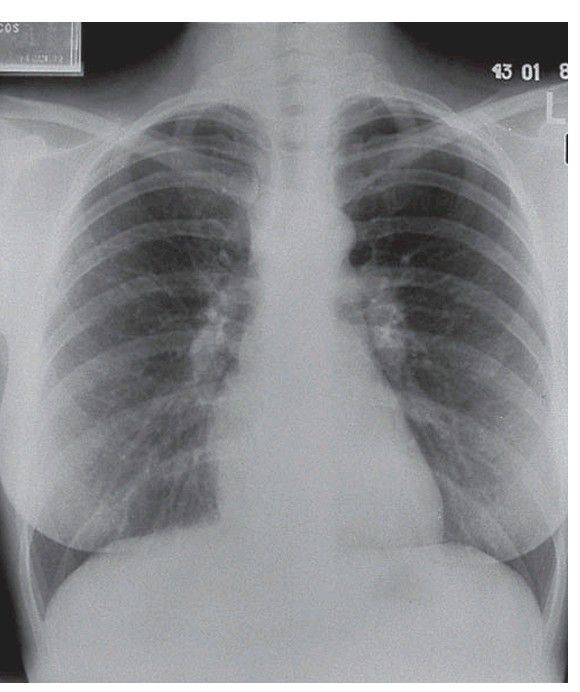

Sarcoidosis

. Prominent hilar lymphadenopathy is the main radiological fi nding, though granuloma formation may be widespread.